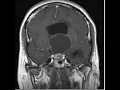

relação íntima com a hipófise a neuro-hipófise sendo uma continuação do infundíbulo hipotálamo e o exame de imagem na ressonância e se nós tomamos o corte sagital exatamente na linha média nós podemos observar aqui e o assoalho do terceiro ventrículo correspondendo ao encontrar a botar aqui um fundinho bruce continuando para compor a neuro impostos e eu vejo que há tumores que se desenvolvem nessa região é um tumor que afeta a região do hipotálamo é o craniofaringioma e foi assunto da minha tese de doutorado fiz pesquisa genética do crânio faringe oma tentando ajudar a obter mais meios

veja na imagem esse craniofaringioma uma porção sólida aqui na cela uma porção cística migrando para cima e acertou derrotarmos sem dúvida comprimido o seu plano provocando aí e no paciente assim não importa alegre é um s10 em algumas funções e estes eram alguns aspectos que nós gostaríamos de discutir de um modo bastante básico e objetivo sobre potara mas que já introduz a compreensão sobre a sua estrutura e a sua função espero que tenham aproveitar ficamos à disposição nos olhos meios de contato que é estão e até uma próxima oportunidade